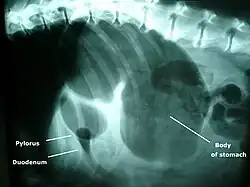

A diagnosis of GDV is made by several factors. The breed and history often gives a significant suspicion of the condition, and a physical examination often reveals the telltale sign of a distended abdomen with abdominal tympany. Shock is diagnosed by the presence of pale mucous membranes with poor capillary refill, increased heart rate, and poor pulse quality. Radiographs (X-rays), usually taken after decompression of the stomach if the dog is unstable, shows a stomach distended with gas. The pylorus, which normally is ventral and to the right of the body of the stomach, is cranial to the body of the stomach and left of the midline, often separated on the X-ray by soft tissue and giving the appearance of a separate gas-filled pocket (double-bubble sign).[5]